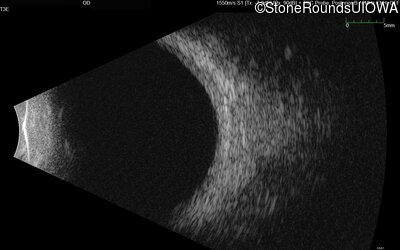

B-Scan Ultrasonography - Left - Light Perception

Exemplar